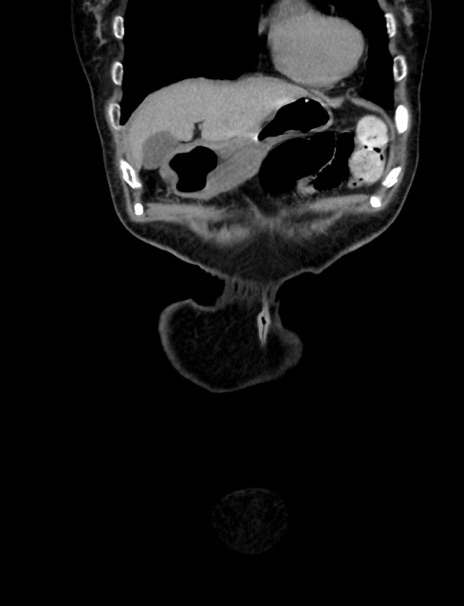

横断像

【症例】70歳代 女性

【主訴】心窩部痛

【現病歴】延髄病変の精査・加療にて神経内科入院中。本日より心窩部痛あり。

【身体所見】右下腹部を中心に圧痛と反跳痛あり。

【データ】WBC 10900、CRP 0.02